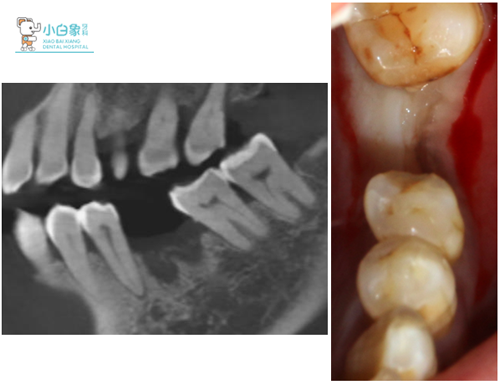

2018年4月18日 36拔除三个月后复诊。

检查:36牙槽嵴丰满,近远中间隙正常,牙龈无红肿。

三月后CT+口内像

2018年4月23日 36必兰局麻下,切开翻瓣,预备种植钉道,植入美格真5.0*10种植体一枚,严密缝合。